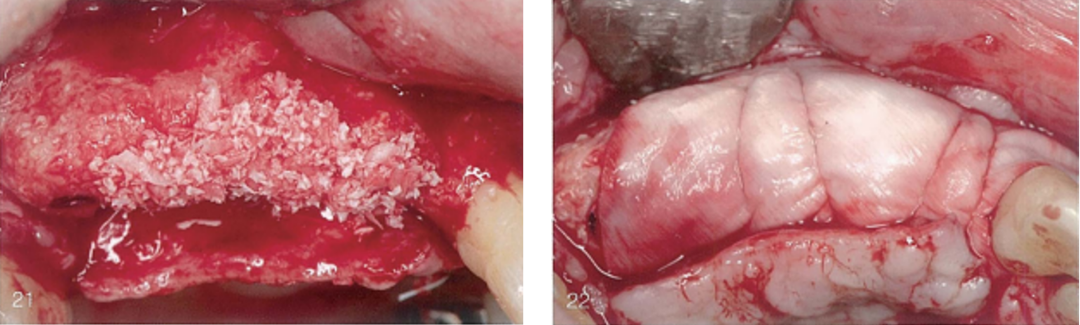

(13)和(14)唇侧观,术区放置多西环素膏的过程与放置后。

(15)唇侧观, 术区冲洗后 ;(16)唇侧观, 术区放置天然胶原膜。

(17)使用PTFE缝线进行双层缝合 。 (18)唇侧观,愈合7个月,术区愈合未见异常。

(19)和(20)唇侧观和牙合面观,骨再生最终效果。可见健康的新生骨,垂直骨有最显著增加,宽度上足以植入种植体。但由于术后感染,垂直向骨增量不够充足。

(21)为了保护术区并改善微小但确实存在的垂直向缺陷,进行第二次骨移植。(22)使用胶原膜做屏障膜并缝线固定以保护并稳固第二次骨移植材料。